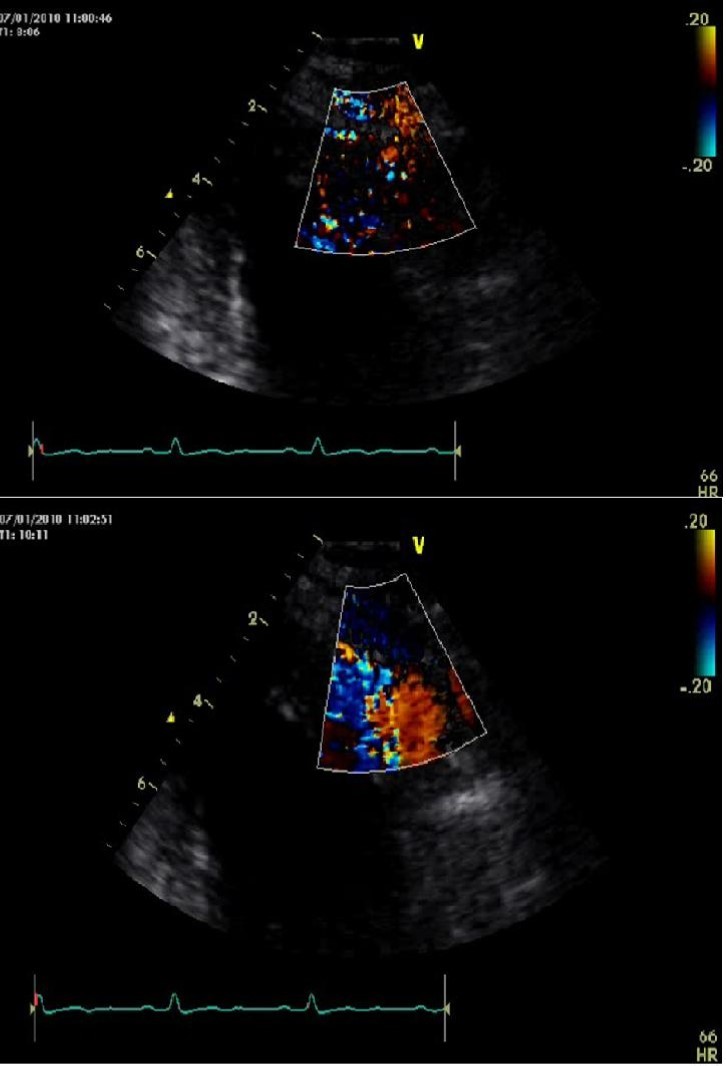

A 62 years old man six years ago underwent coronary angiography due to atypical chest pain. No coronary stenosis was observed while multiple coronary fistula coming from middle tract of left anterior descending (LAD) artery and draining to left ventricle cavity were detected (Figure 1). At discharged, he undertook antiaggregant therapy and no fistula’s closure indication was advised.

Figure 1.A/B. Left anterior descending artery fistula in left ventricular cavity: an angiography perspective.

A/B. Left anterior descending artery fistula in left ventricular cavity: an angiography perspective.